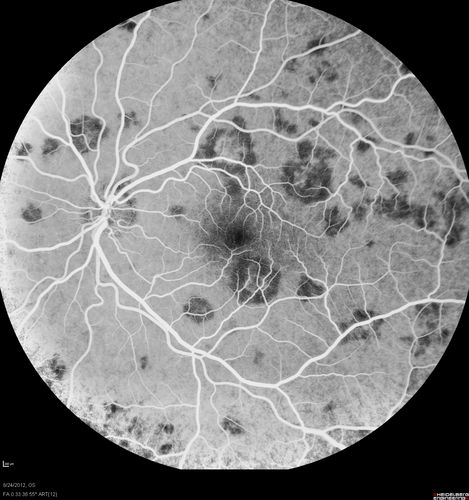

Acute Posterior Multifocal Placoid Pigment Epitheliopathy - APMPPE - Fluorescein Angiogram

25-year-old man with one and half weeks ago he woke up with night chills.   Also around that time his joints started hurting him.  He also has headaches, although the headache at this point is not severe.  His vision has been changing for about the last week and a half.  He sees some spots in his vision and they are blurred spots.  They are not in the central vision.

VISUAL ACUITY:  OD 20/32,  OS 20/32